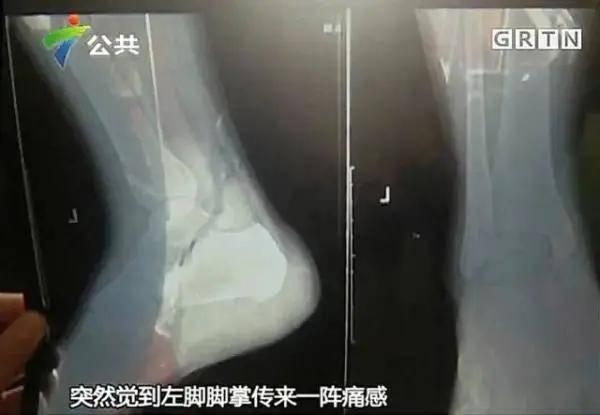

紧急救治,骨折严重

幸运的是,现场有专业的医疗团队。他们迅速对小李进行了救治。经过检查,医生发现小李的大腿骨折非常严重,需要立即进行手术。手术过程中,医生们小心翼翼地为他接上了断裂的骨头,并固定好。